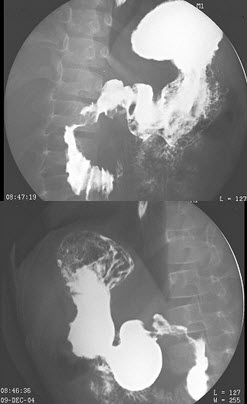

55、单项选择题

女,50岁,胃体贲门癌术后3月余,自诉进食有梗阻感,结合图像,最可能的诊断为()

A.吻合口通畅

B.吻合口狭窄

C.吻合口溃疡

D.吻合口充盈缺损

E.吻合口穿孔